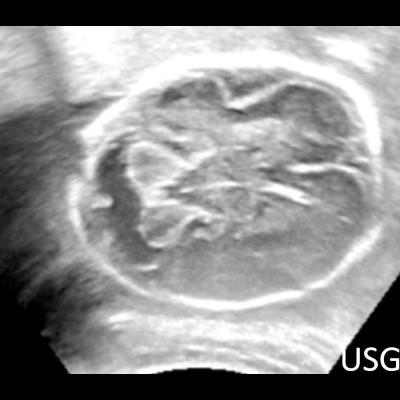

- A) USG incelemede serebral kortikal yapılar düzleşmiş (ok), gyrus sayısı azalmıştır (ok). Kalın ve ekojenik korteks mevcut olup korteks -beyaz cevher ayrımı silik görünümdedir. Posterior fossada ekstraaksiyel BOS mesafesi artmış görünümdedir (ok).